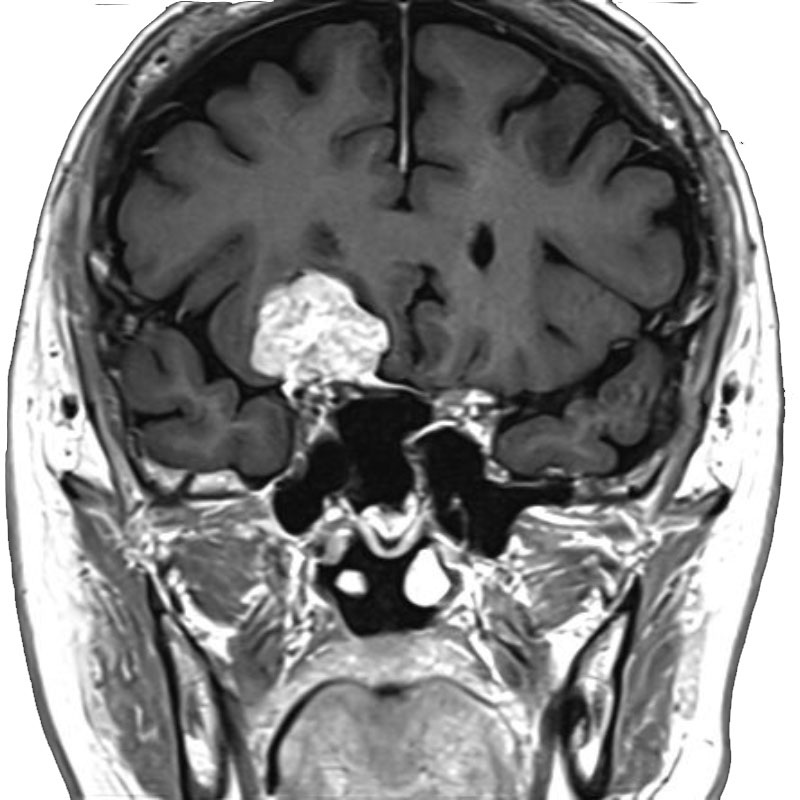

脳動静脈奇形

血管塞栓術

松田/濵田/元永